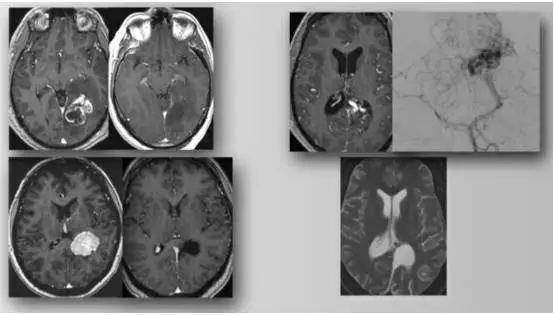

图3. 房部内侧壁和三角区的胶质瘤(左上图),脑膜瘤(左下图)和动静脉畸形(右图),均可采用PITTA入路(包括术后影像)。